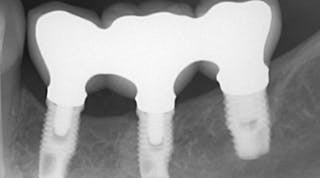

توضیحاتTEDMA, HEGMA, BISGMA and BPA_freeاسپلنیت کردن ایمپلنت و ثبت بایتاین محصول از ترکیب رزینهای خاص ساخته شده که یکی از سخت ترین ثبت بایتها را ایجاد میکند.سختی بسیار بالا و مقاومت در مقابل فشارمقاومت خمشی بالاانقباض خطی بسیار ناچیزتیکسوتروپیک و قوام مناسب برای جلوگیری از جاری شدن بین دندانهابدون هرگونه پسماند و آثار اضافی پس از عمل پخت در کورهکاهش واکنش گرمازا هنگام سفت شدنرنگ آبی با کنتراست بالا (تشخیص آسان توسط چشم و لیزر)برداشت آسان اضافاتزمان کاری: 40 ثانیهفیکس کردن محل ایمپرشن کپینگ روی ایمپلنت و جلوگیری از جابجایی ایمپلنت، قبل از قالبگیری نهاییثبت بایت جهت تشخیص موقعیت دندانهای فک بالا و پایین، مخصوصا در مواردی که بیمار اوکلوژن نرمال ندارد (مال اوکلوژن)حاوی یک کارتریج، 50میلیلیتر و10 عدد سری میکسرسختی بسیار بالاتیکسوتروپی و قوام مطلوبقابلیت اسکن با tactile lecture/optical/laser systemویسکوزیته قابل تحمل برای بیمارثبت عالی جزئیات (15µ)تغییرات ابعادی بسیار کم (~0.02%)برش آسان اضافات